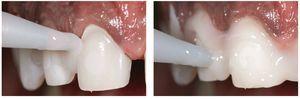

En virtud del protocolo hemostático preciso con hilos finos, el tejido blando estaba sano al cabo de 21 días. Antes de la inserción definitiva de las restauraciones cerámicas se procedió a una prueba en boca para escoger el color ideal del cemento de resina. Tras la retirada de los provisionales se eliminó mediante discos de óxido de aluminio (Soft-Lex, 3M Espe, Seefeld, Alemania) la capa adhesiva que se encontraba en las superficies grabadas. Dado que se preparó únicamente en la zona del esmalte, fue posible llevar a cabo la prueba en boca del paciente sin anestesia.

A fin de obtener un resultado óptimo, los procesos de adhesión en caso de carillas laminadas muy finas requieren un alto grado de atención. En este caso se utilizó para la prueba en boca un material adecuado con una pasta, con objeto de escoger el color más indicado para el cemento de resina. La pasta para la prueba en boca es un gel de glicerina hidrosoluble que simula el resultado terminado. La figura 32 muestra la diferencia de color durante la prueba en boca.

Fig. 32. El color y la adaptación se comprueban mediante una pasta para prueba en boca a base de glicerina (Variolink Veneer Try-in Paste, Ivoclar Vivadent). Se probaron dos colores distintos: uno de baja claridad (LV-3) para el incisivo central derecho y uno con un grado de claridad elevado (HV+3) para el incisivo central izquierdo. El paciente participó activamente en la elección del color.

Se probaron distintos colores de pasta con mayor y menor intensidad (Variolink Veneer Try-in Paste, Ivoclar Vivadent). El paciente, el protésico dental y el odontólogo se decidieron de común acuerdo por un cemento de resina fotopolimerizable con un alto grado de claridad (Hohes Value HV+3, Variolink Veneer, Ivoclar Vivadent) para cementar definitivamente las restauraciones (fig. 33). El cemento de resina fotopolimerizable es preferible a las resinas de fraguado dual o autopolimerizables para el cementado de carillas laminadas, en virtud de su estabilidad cromática a largo plazo.

Fig. 33. Las cuatro carillas laminadas de los dientes anteriores realizadas en disilicato de litio se colocaron con una pasta de prueba en boca de gran claridad. Éste fue también el color de pasta finalmente seleccionado.